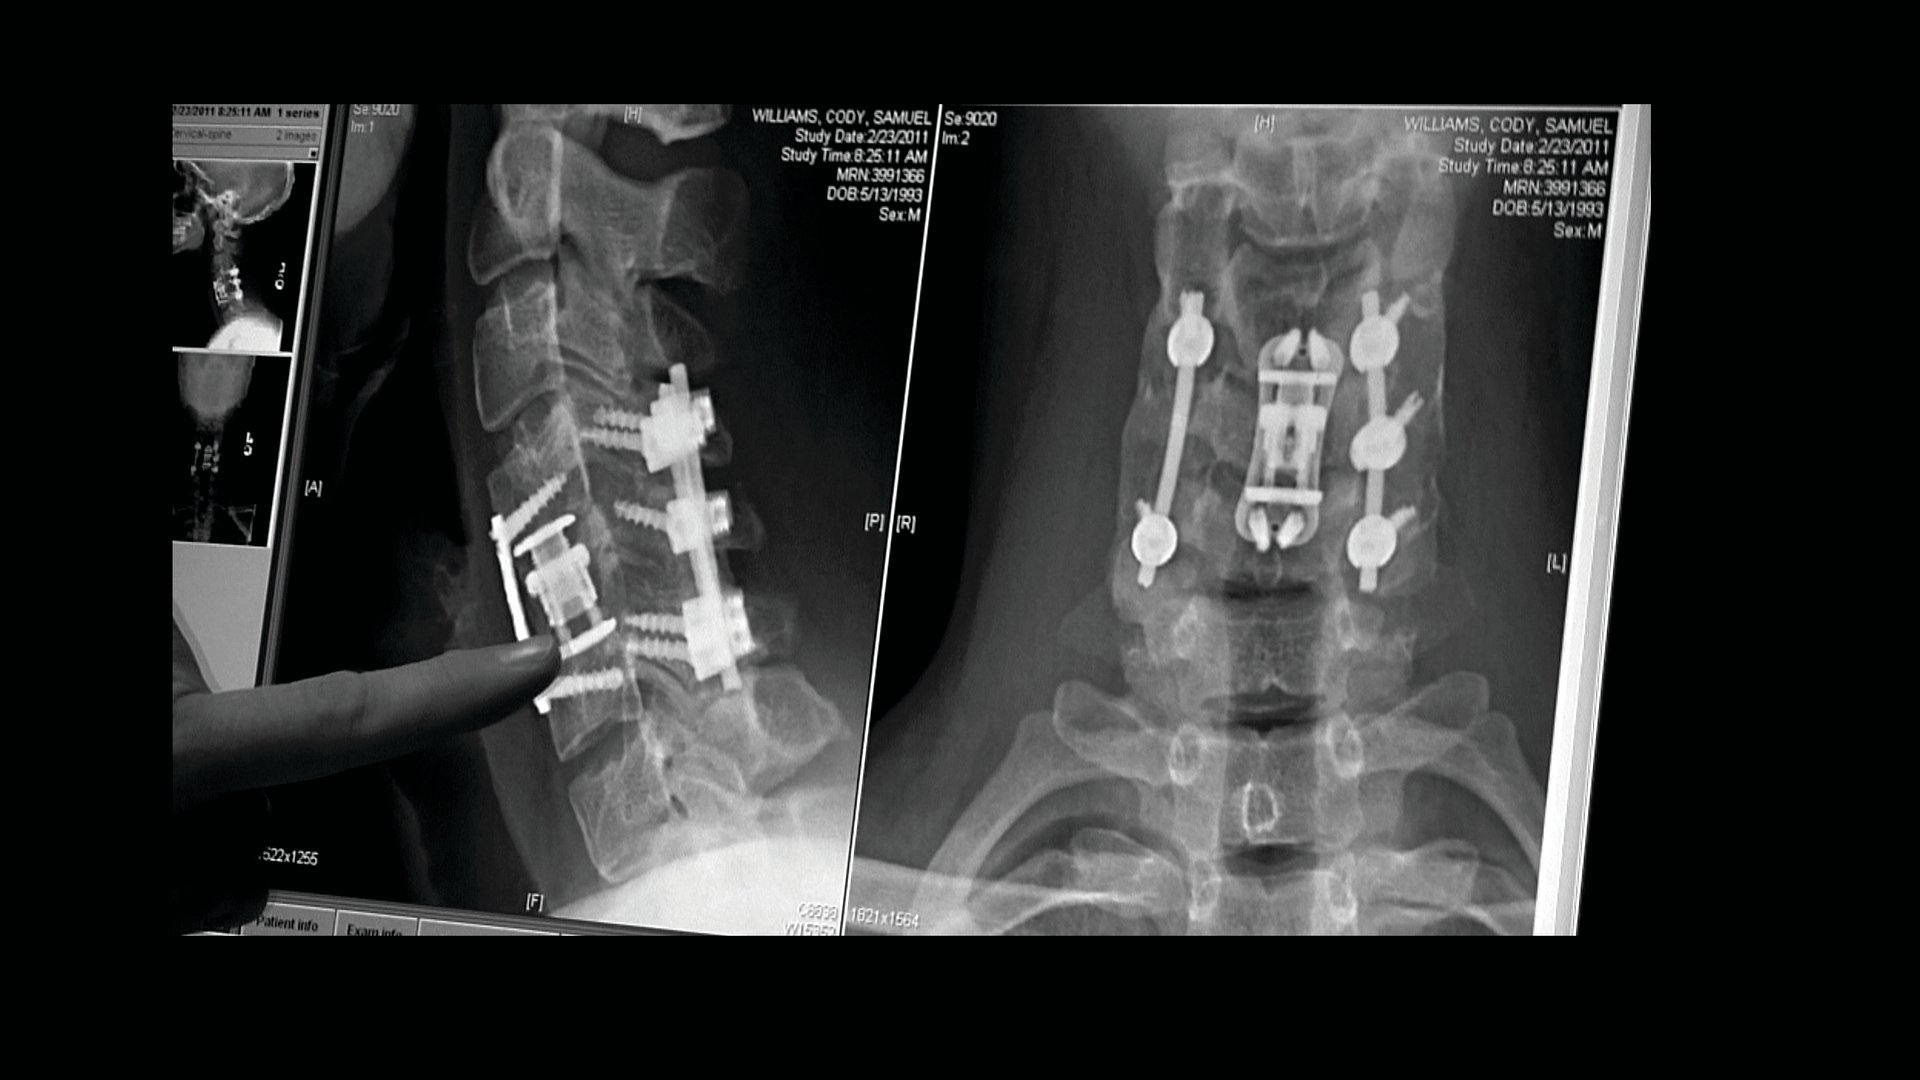

The Hill Chris Climbed: The Gridiron Heroes Story

2011 90 мин

Тейлор Китч, Eddie Canales, Chris Canales, Al Michaels, Cody Williams